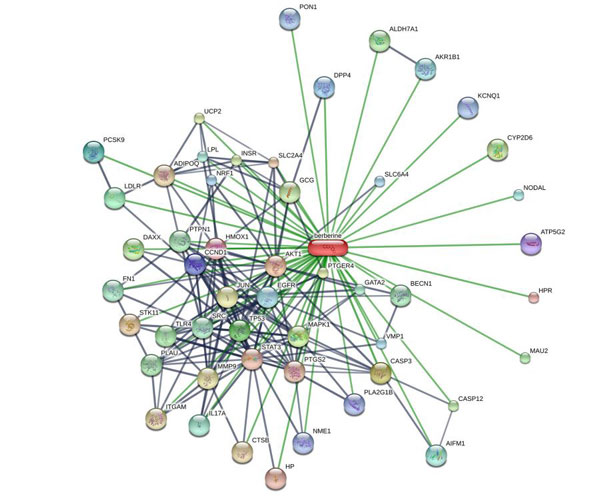

Des études récentes démontrent que la berbérine est un candidat de rêve (1) au traitement du diabète. Elle présente des effets anti-hyperglycémiants et anti-hyperlipidémiques remarquables tout en influençant positivement le poids (2-5). La seule raison qui explique pourquoi elle n’est pas encore connue de tous c’est que son mécanisme d’action précis échappe toujours à la recherche. En fait, contrairement aux médicaments, il semble qu’elle puisse influer sur de nombreux mécanismes associés au contrôle de la glycémie, à la lipogenèse (le processus de réserve énergétique des cellules graisseuses) ou à la sensibilité à l’insuline. Le schéma ci-dessous montre l'influence qu'elle exerce sur un nombre considérable de facteurs et récepteurs cellulaires.